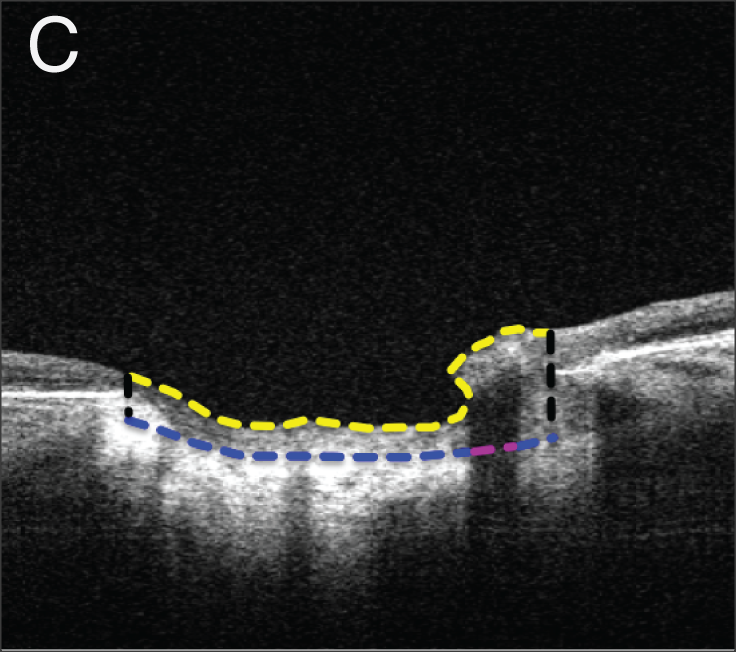

• IOP Elevation Reduces Schlemm’s Canal Cross-sectional Area

• L Kagemann, B Wang, G Wollstein, H Ishikawa, JE Nevins, Z Nadler, IA Sigal, RA Bilonick and JS Schuman

• Investigative Ophthalmology and Visual Science, 55(3), 1805-1809, March 2014.

image